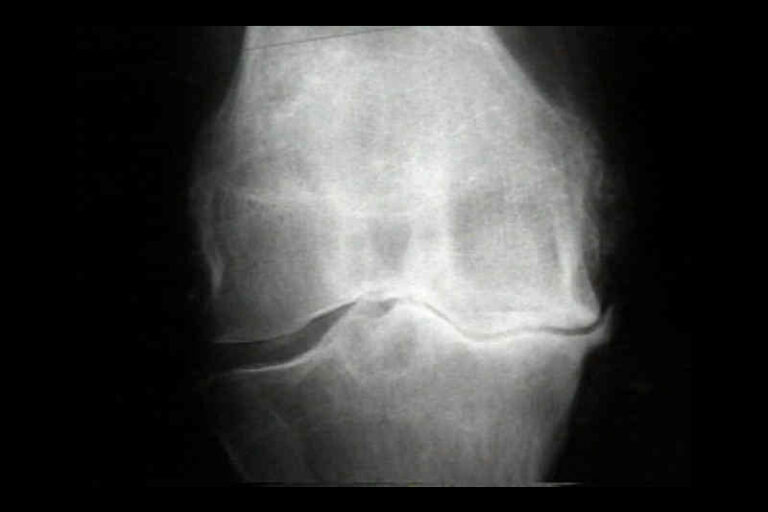

「鶴膝風」是個中醫病名,是指膝關節退化持續惡化,到了後期出現膝關節周圍腫脹、變形,周邊的肌肉萎縮,在外觀上看到膝蓋腫大變形,而上下的大腿、小腿變得瘦小,狀如鶴膝,故名「鶴膝風」。到了這個階段,患者通常都有膝關節屈伸困難,每當上下樓梯、上落斜路、下蹲時都會感到疼痛,當早上起床或休息後膝關節會僵硬,每當天氣變化時常誘發膝痛,嚴重影響病者的起居作息,部份甚至因膝關節畸形影響步態而要使用手杖輔助支撐身體。